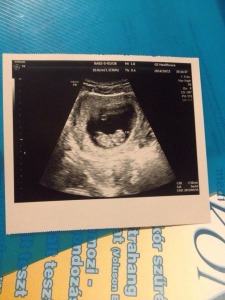

Hazamentünk és annak tudatában, melyik orvost ajánlotta Gabika, neki láttam kutakodni a doki után, mert persze nekem azonnal, de minimum másnap látnom kell ezt az orvost. Kapóra is jött, hogy másnap Ő volt az ügyeletes ultrahangos… Reggel 9 órakor én bizony már a soromat vártam a többi kismama mellett, hogy csekkoljam kivel van valójában dolgunk. Egész hamar sorra kerültem, bementem kezet ráztam a dokival és elhadartam ki vagyok és mit akarok. Ultrahangot a halacskámról, de most rögtön (na jóóó, ezt csak gondoltam 🙂 ), de megkaptam amit akartam, a kis halunk mar nem is kis hal hanem valami egész más :). Most is pozitívan távoztam és büszkén nyomtam az Apuka kezébe az újabb képet a porontyról.